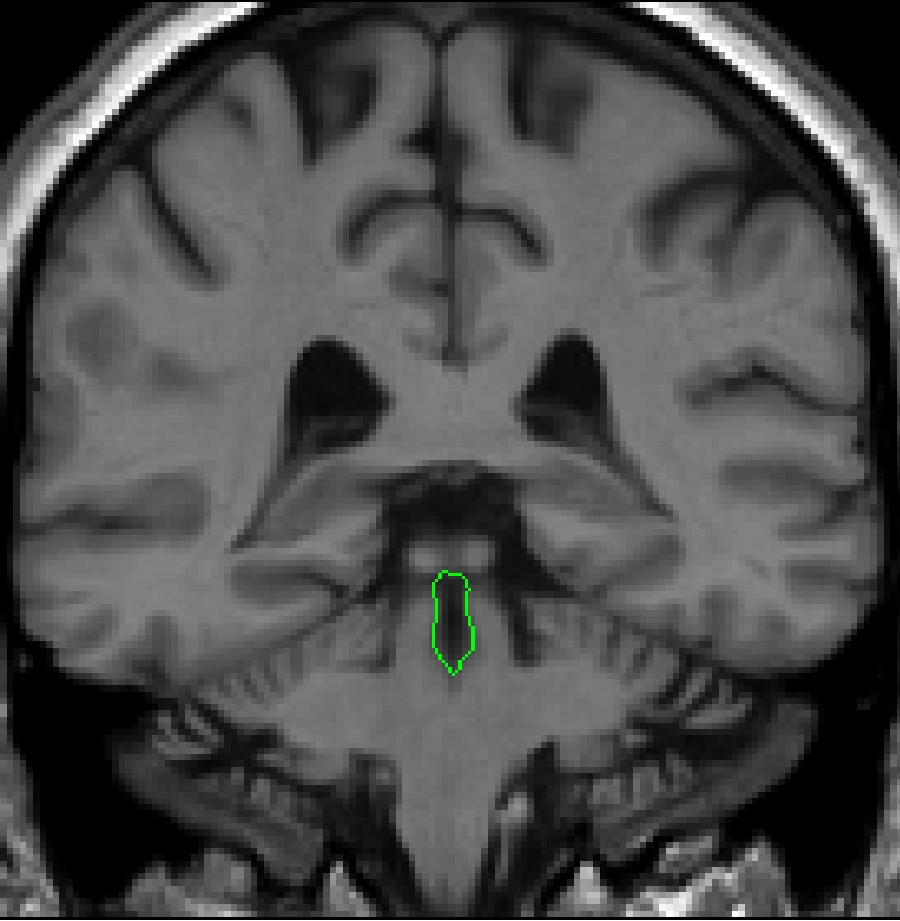

Part II - fourth ventricle in the brainstem

As you move posteriorly, you will begin to see the actual beginning of the

fourth ventricle. The small circle that is the aqueduct will begin to elongate.

Continue to use the histogram method; draw your box between the CSF of the

fourth ventricle and the surrounding brainstem tissue. Modify as necessary

with the intensity contour function. As the fourth ventricle continues posteriorly,

it will start to widen. A histogram should be taken between the CSF of the

fourth ventricle and the surrounding brainstem tissue. Often this histogram

will not yield the dorsal border of the 4th

ventricle.

Brightening the screen will enable you to see this border. It should be drawn

in using the draw function, and then attached to the contour given by your

histogram.